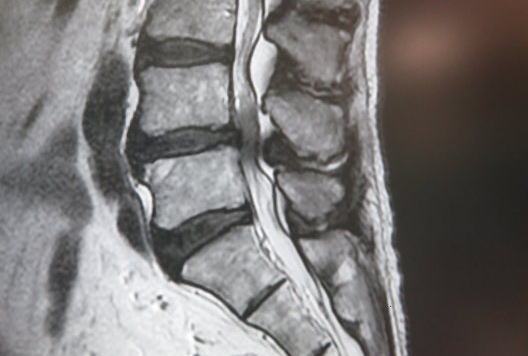

なぜ、医師選びがそこまで重要なのでしょうか。脊柱管狭窄症の手術は、「体の中の極細トンネル内の工事」です。しかも、そのトンネルの中には、神経という超デリケートな配線がぎっしり詰まっています。その様子を想像してみてください。